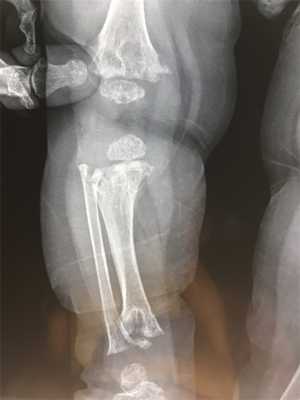

При диагностике врачи обращают внимание на характерное поражение проксимального отдела шейки бедра. Кости имеют неправильную форму, недостаточную плотность, низкое содержание кальция и микроэлементов. На рентгеновских снимках заметны неровные контуры, расширенные участки эпифизов.

Для пациентов с типом MакКьюзика характерны хроническая анемия, патологии кишечника. На рентгеновских снимках заметно увеличение метафизов в области коленного сустава. В детском возрасте нередко встречается двояковыпуклое строение позвонков, которое постепенно исчезает после взросления.